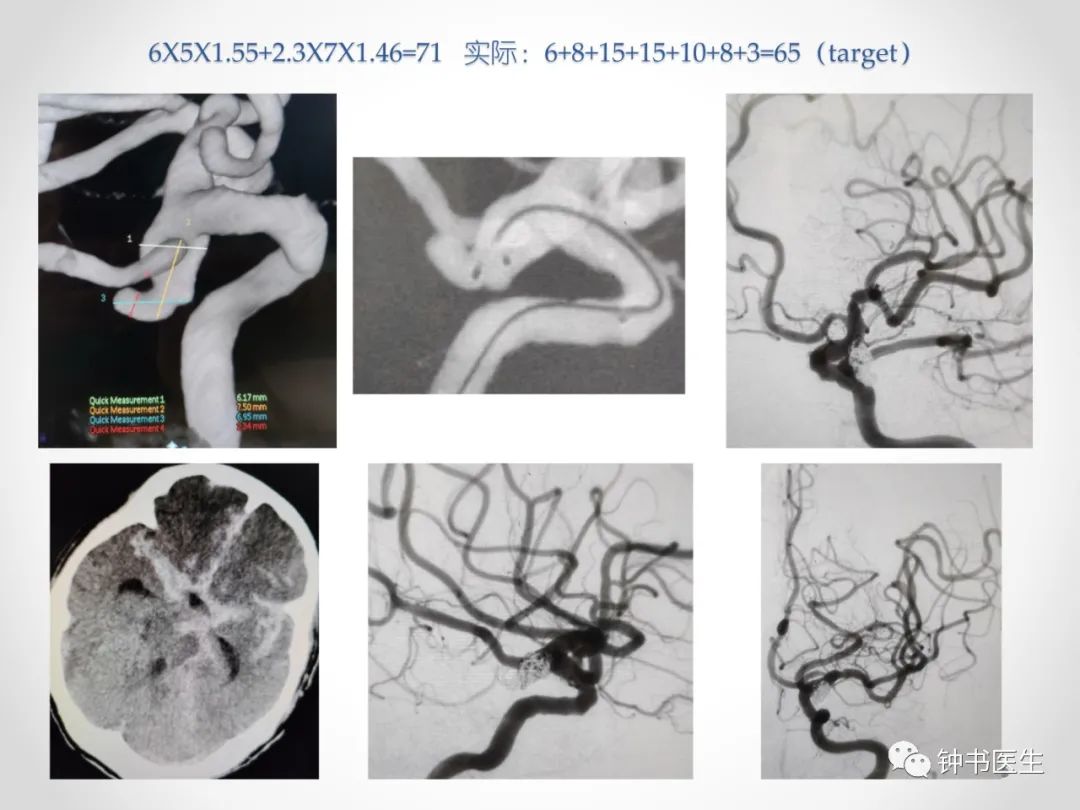

长x宽x1.X=弹簧圈总长度

1.X:X为动脉瘤平均直径

成篮圈直径长度比:4以下2倍;4~7为3倍;7以上大于3倍;取短径加1倍,取长径减1倍!

长度分布:前1/3占总长度2/3;中间1/3接近总长度1/3;首圈为成篮不宜过长;

AXIUM、泰杰、target、galaxy、matrix2、佳奇、微创等

增加0.2 :AXIUM PRIME、Microvention、Visee